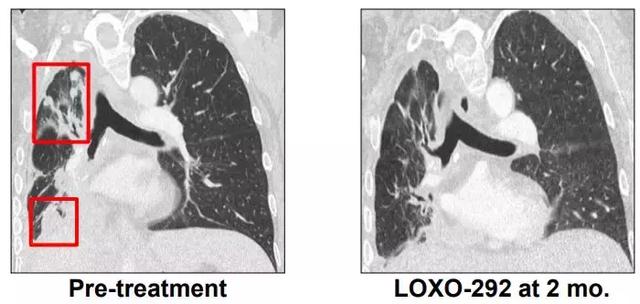

M女士走圖無路的情況下接受了基因檢測(cè),發(fā)現(xiàn)了KIF5B-RET融合,開始接受600 mg BID靶向藥 alectinib治療(PR,7個(gè)月),由于腦轉(zhuǎn)移進(jìn)展增加至900mg BID,后腦轉(zhuǎn)移癥狀嚴(yán)重,M女士接受了LOXO-292治療,于是奇跡出現(xiàn)了,治療兩個(gè)月后,M女士肺部的病灶明顯好轉(zhuǎn),腦部病灶幾乎全部消失!

?